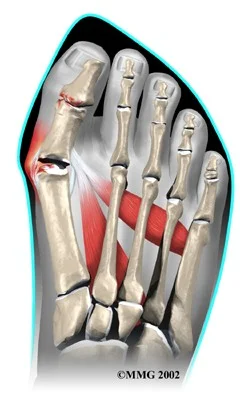

Plantar Fasciitis

- Definition → inflammation of the plantar fascia

- In the posterior 2/3 of the foot

- Painful & sometimes disabling

Causes - Plantar Fasciitis

- Insidious (not clear H/O an incident)

- Some times:

- Increased sport / repetitive stress

- Change of footwear

- Change of walking surface

- Gain of weight (pregnancy, obese)

- Prolonged standing Z

- Connective tissue disorders (as D.M, Gout, …)

bunion

- Bunion may be (usually) inflamed / painful